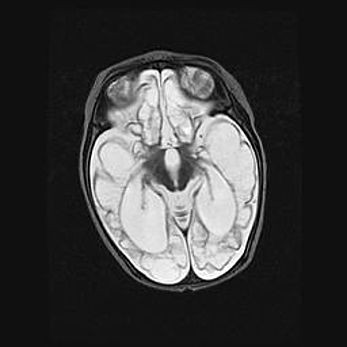

Наружная гидроцефалия с возможной атрофией височных областей.

Возраст: 28 дней

Вес: 3670 г

Пол: мужской

Окружность головы: 38 см

Срок гестации: 40 недель

Гидроцефалия головного мозга у новорожденных – это заболевание, которое характеризуется скоплением избыточного количества спинномозговой жидкости в желудочковой системе головного мозга в результате затруднения её перемещения от места выработки к месту поглощения в кровеносную систему или вследствие нарушения абсорбции. При открытой наружной форме гидроцефалии у новорожденных расширяются и переполняются субарахноидные пространства.

При нормотензивных  формах,  которые,  как  правило,  являются  следствием  перенесенных ишемических  повреждений  паренхимы  мозга,  возможно  сочетание микроцефалии  с нормотензивной гидроцефалией. В основе данных изменений лежит атрофия больших полушарий с преимущественной  локализацией  в  лобно-височных  областях.